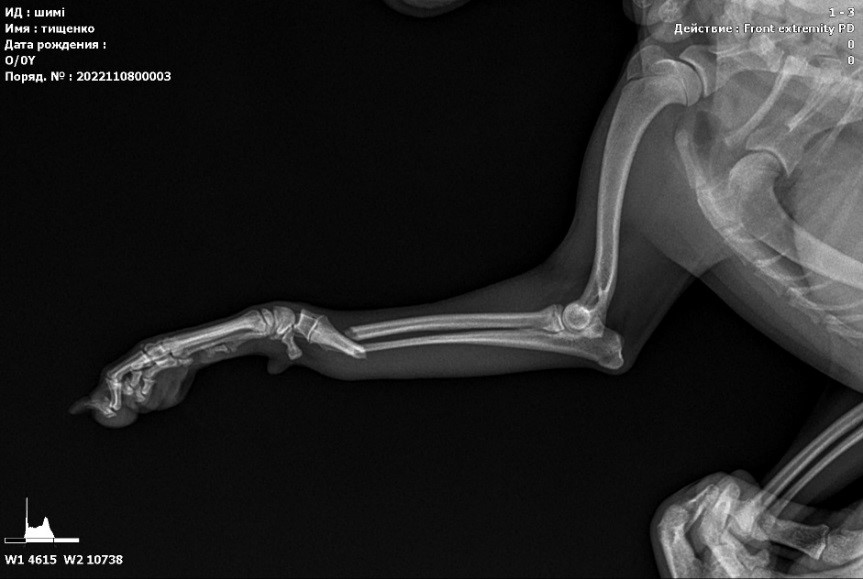

Заболевания позвоночника у домашних животных: диагностика и лечение

Раздел: Визуальные истории